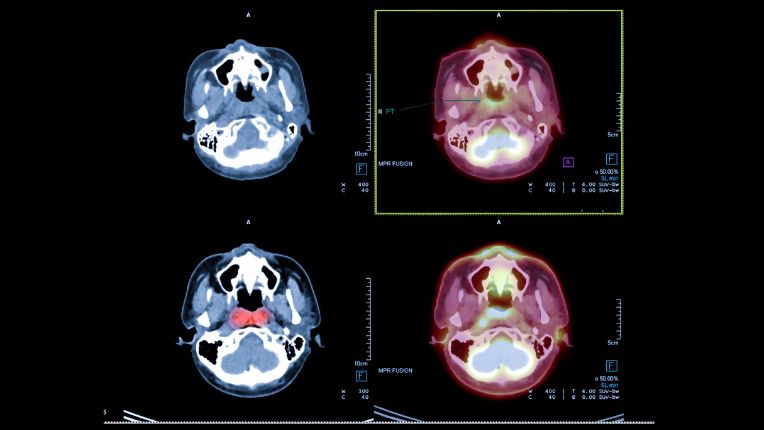

Le cancer du nasopharynx est un cancer des voies aérodigestives supérieures (VADS). Il s'agit d'une pathologie considérée comme peu fréquente. Les traitements proposés en première intention sont souvent la radiothérapie et la chimiothérapie.

L'oto-rhino-laryngologie (ORL) est une spécialité qui traite de toutes les pathologies de la tête, du cou et en particulier du nez, des oreilles et de la gorge.